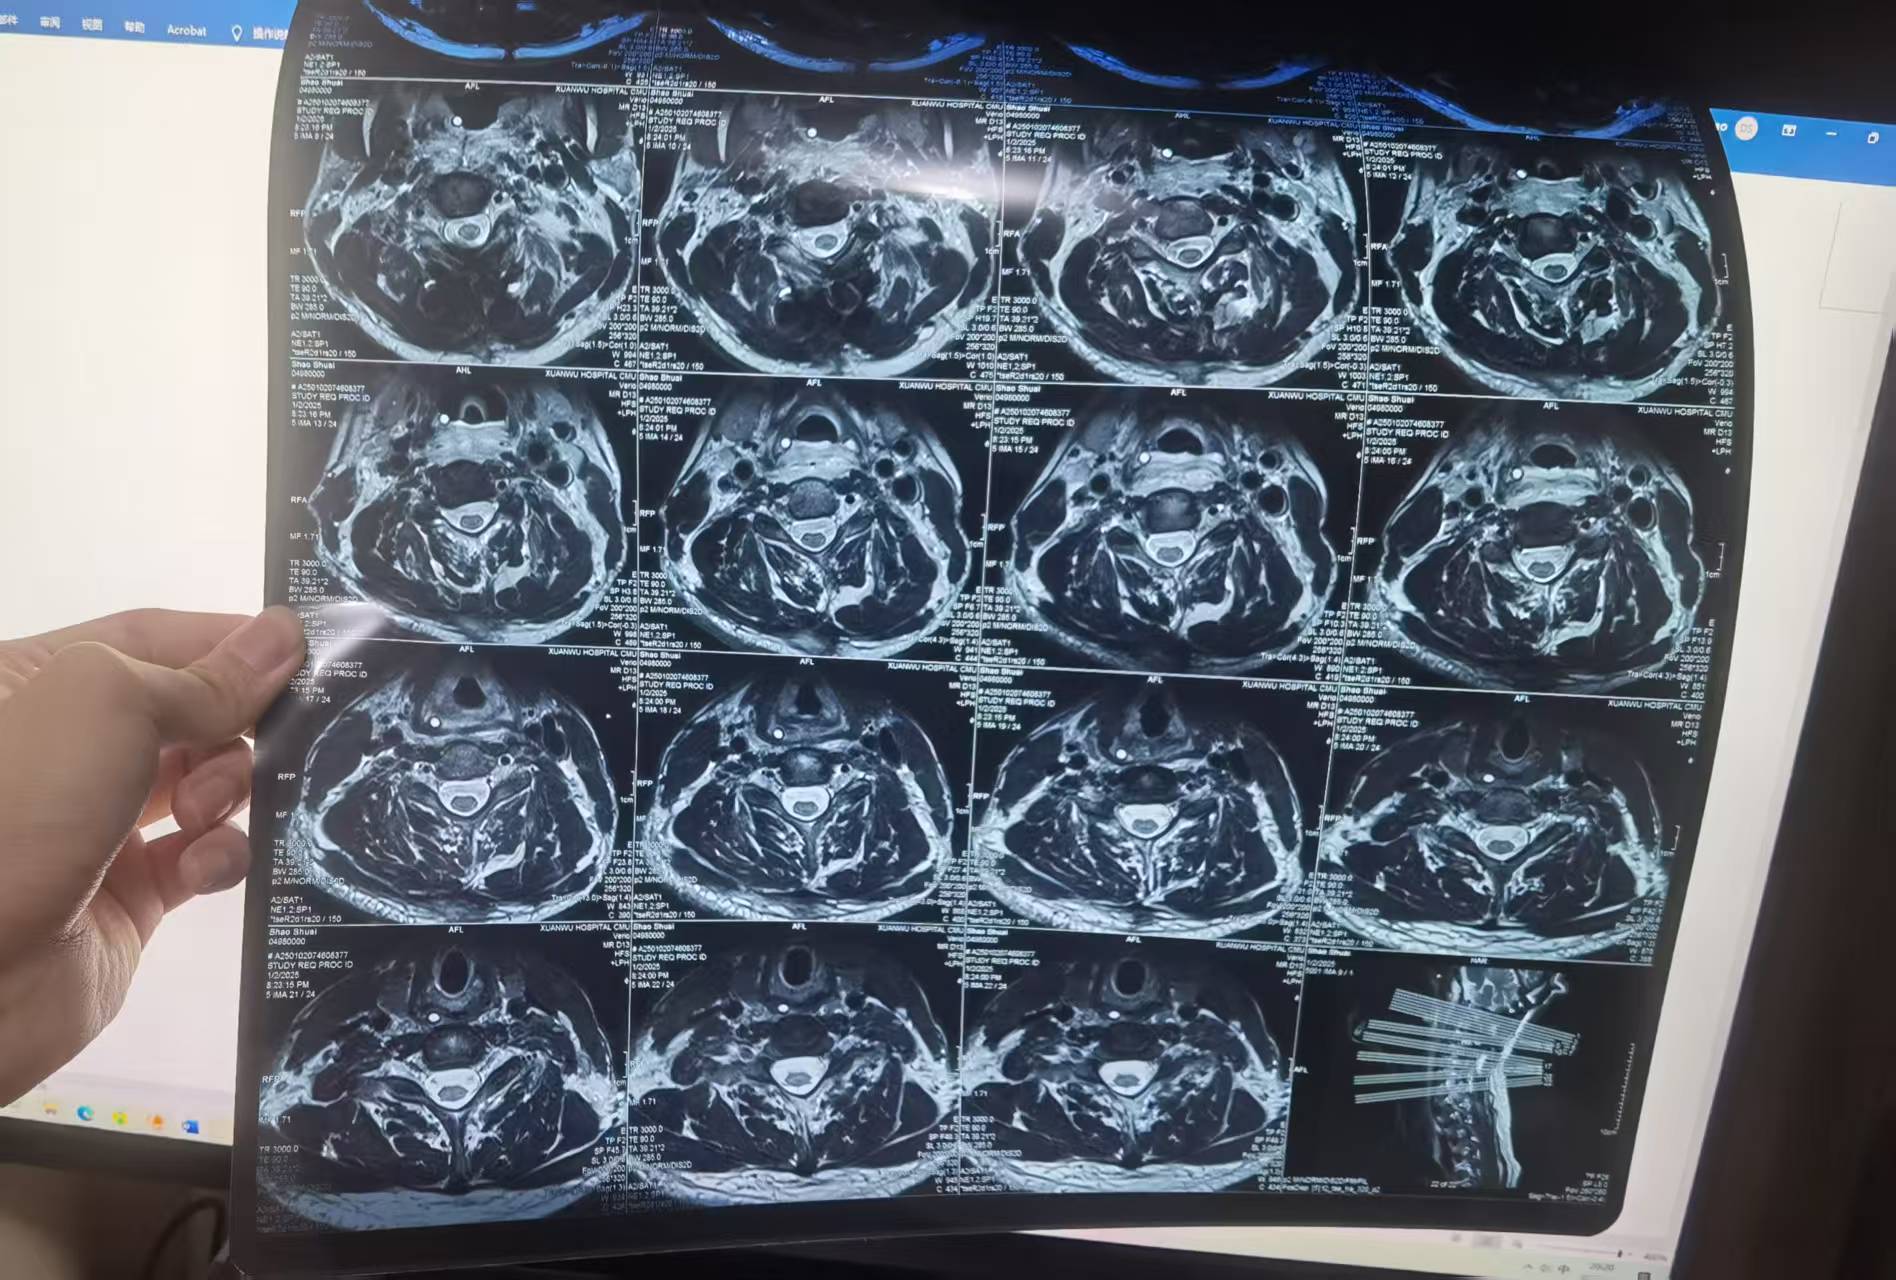

• 诊断:寰枢椎脱位

• 日期:2024.12.31

• 医院:宣武医院

• 主刀:陈赞,段婉茹一助

• 术后状况:切除齿状突,效果良好

• 术后影像: